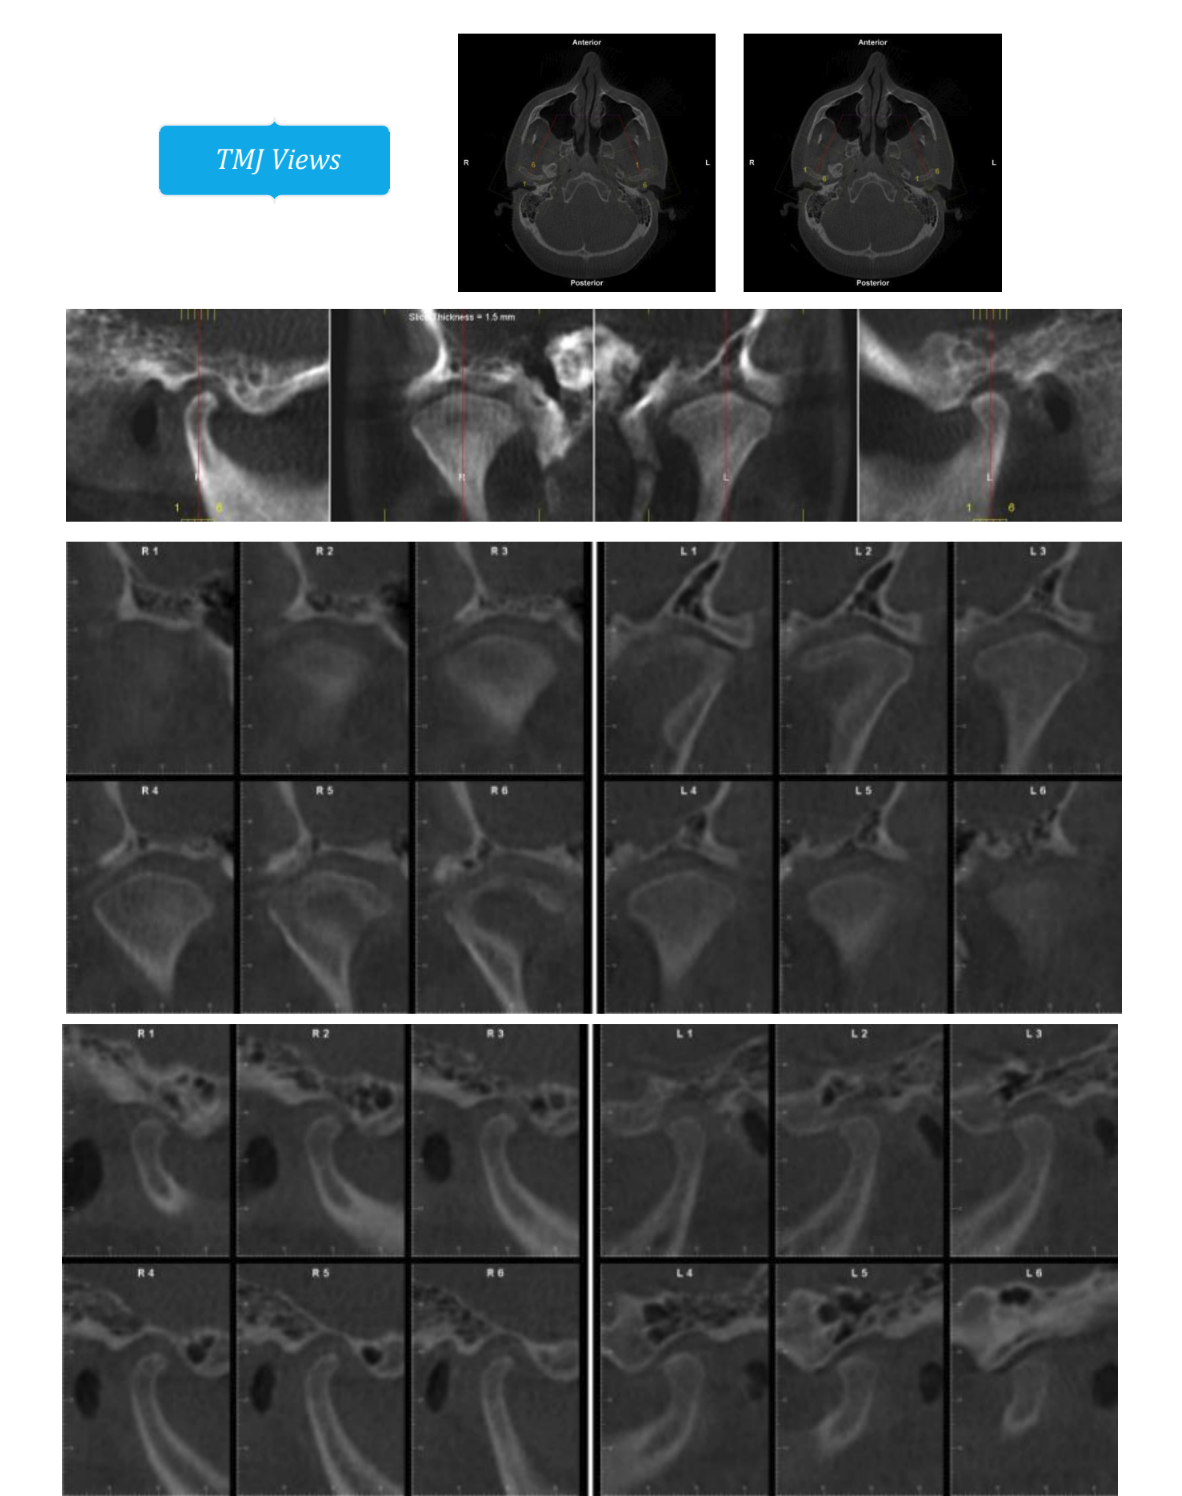

They are planning on doing a segmental 3-piece Lefort 1 which should give me about 5mm of expansion and 8mm of advancement, along with a CCW rotation of a few degrees (my dumbass forgot to ask how many) and a BSSO mandibular advancement of 12mm.

Feel free to ask any questions, also if any autists out there want to make comments about my scans, current appearance and my surgery plans then please do so.